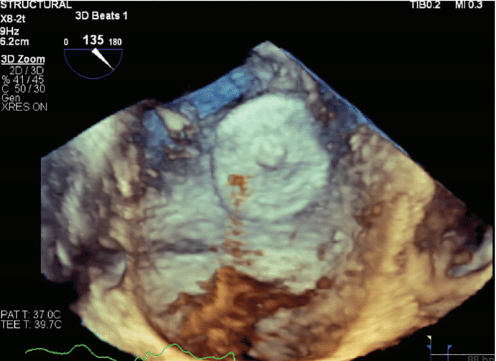

A 78-year-old woman was referred to Northside Hospital Heart Institute for possible LAAC. She had a history of coronary artery bypass grafting (CABG) over 5 years ago, permanent AF with history of atrioventricular node ablation, and permanent pacemaker implantation. Her CHA2DS2-VASc score was 5 due to hypertension, age >75, diabetes, and vascular disease. This placed her at high risk for stroke, but her cardiologist deemed her not to be a good candidate for long-term oral anticoagulation due to intracranial hemorrhage with multiple falls. An operative report of the CABG was obtained, but the report showed only 3-vessel bypass with no report of LAA ligation. Computed tomography (CT) with contrast of the heart was also obtained, which is standard practice for many of our LAAC procedures, especially for patients who have had prior cardiac surgeries. There was a 5.3-mm leak noted at the surgical closure at the base of the LAA (Figure 1). This leak was too large to close with endovascular coils, and there was concern about using an endovascular plug due to length of the leak and possible effects of radial forces over time in the channel. The Amplatzer Amulet device was chosen for this case, with the plan to place the lobe inside the LAA and place the disc covering the channel with forces after closure to be axial in direction. The procedure was performed under general anesthesia and transesophageal echocardiography (TEE) imaging. LAAC procedures at Northside Hospital Heart Institute are usually performed using TEE guidance only, with no use of contrast, since our noninvasive physicians (Drs John Ricketts and Colin O’Brian) provide imaging for transseptal puncture, device deployment, and post-imaging for any leaks, including 3D TEE at every step when needed. Due to the unusual nature of this anatomy, we performed contrast fluoroscopy of the LAA. Figures 2A and 2B show the pre-implant and periprocedural TEE images. Figure 3 shows the contrast injection through the 12 French Torque Vue 45-degree Amulet delivery sheath (Abbott) and the Glidewire (Terumo Interventional Systems) in the LAA. The placement was primarily guided by TEE imaging. The smallest size (16 mm) Amulet device was chosen for closure. Figure 4 demonstrates placement under fluoroscopy. Figures 5A and 5B demonstrate closure using TEE imaging. Post procedure, the patient was placed on aspirin and clopidogrel for 3 months. Once adequate seal is confirmed at 3 months, the goal is for the patient to switch to aspirin (81 mg).